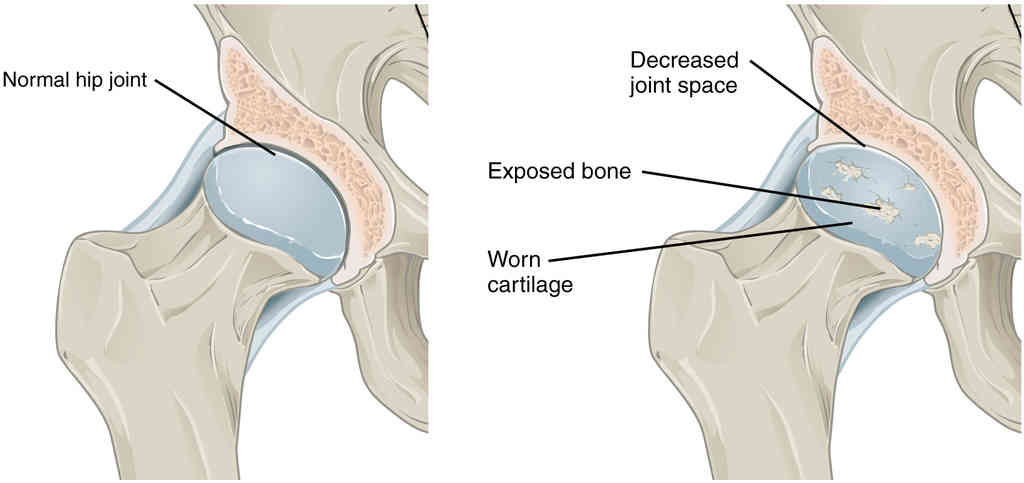

This page is under construction. For now, it is just a resource of the images found in the OpenStax Anatomy and Physiology Handbook. It wil slowly change into a revision tool. Each slide has a number. Use this to refer to the slide. When completed, it will have an unlabelled section, with labelled slides in parallel. On the unlabelled slides, write your answer and use the labelled slide to assess yourself. Keep track by also noting the number on each slide. Improvement at each attempt is important, more so than full marks on a first attempt.